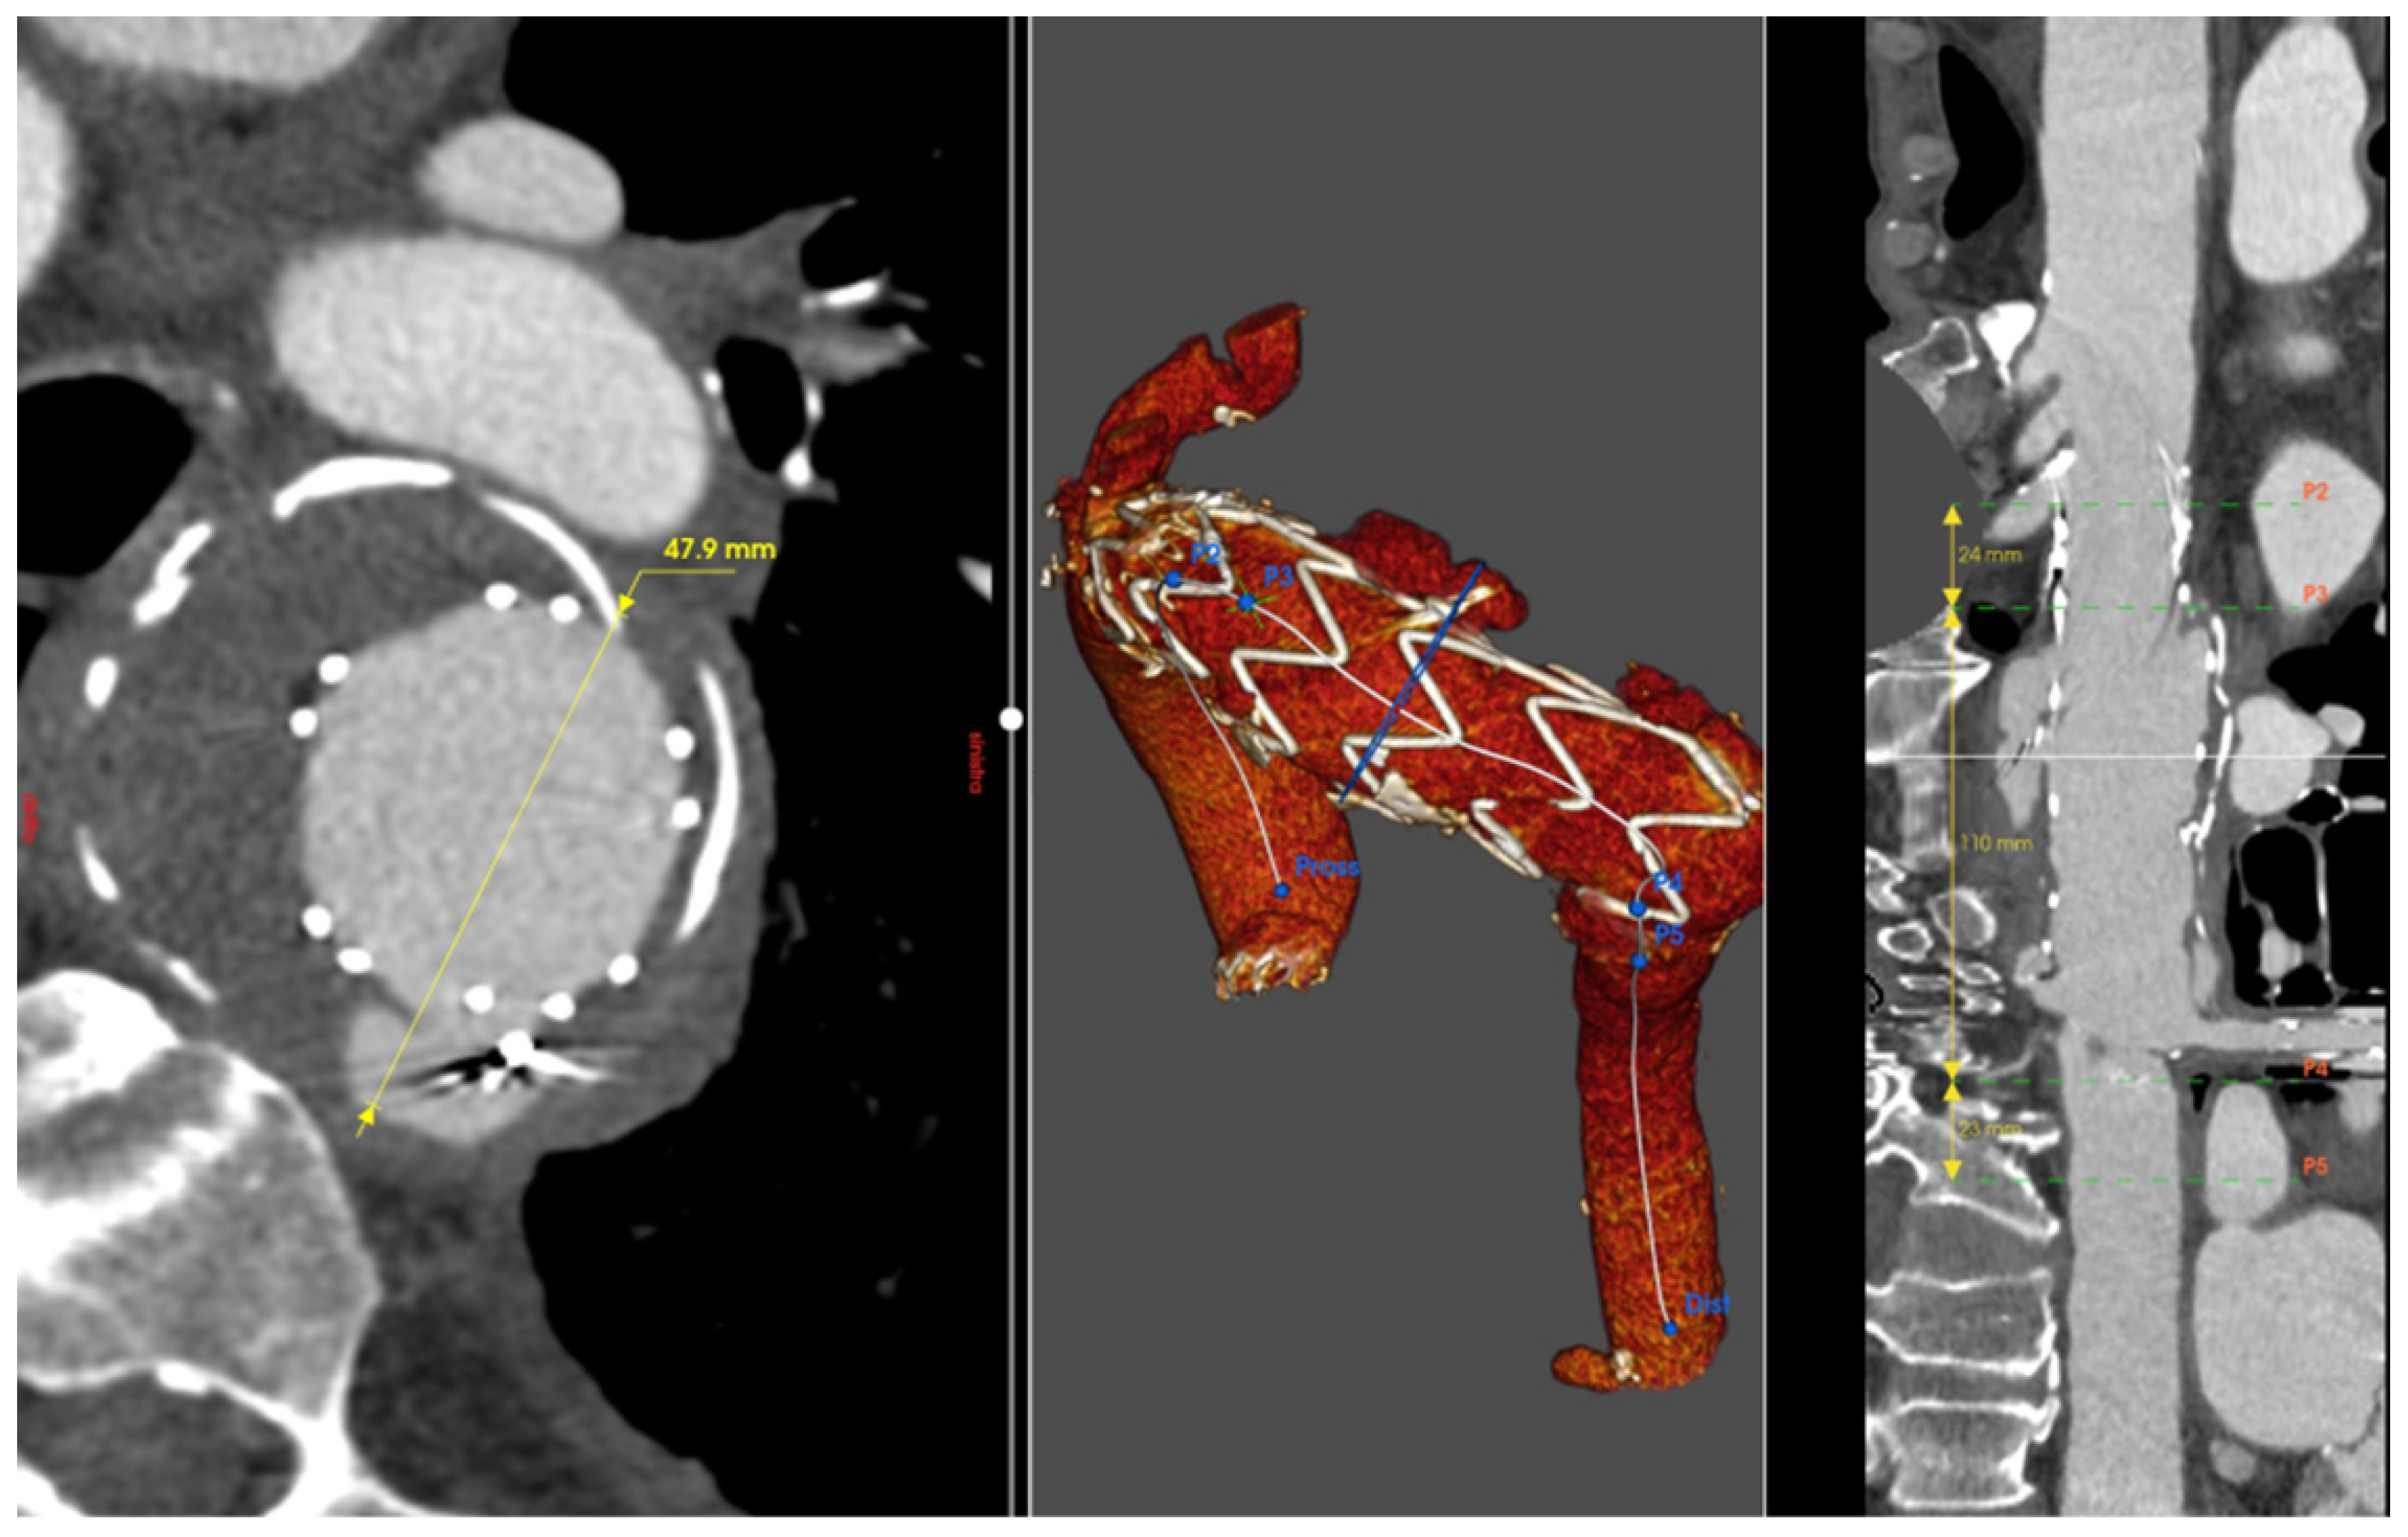

An 85-year-old gentleman underwent left common carotid–left subclavian artery extra-anatomical bypass followed by TEVAR for a distal aortic arch aneurysm in 2014. Subsequently, the development of a type IB endoleak required further TEVAR in 2019. Then, coil embolization was required for a type IA endoleak in 2020. Nevertheless, follow-up imaging investigation showed further development of type IA endoleak up to 83 mm in diameter with significant dilatation of the proximal aortic arch and aneurysm of the ascending aorta at 58 mm in diameter. The echocardiographic assessment revealed severe aortic regurgitation. Significant comorbidities included previous myocardial infarction requiring percutaneous intervention and stenting of the right coronary artery, chronic renal impairment, previous neurological event, giant cell arteritis, and rheumatological disease. The presence of aortic valve disease and the severity of the aortic arch aneurysm made a total endovascular approach an unsuitable option. In contrast, the patient’s comorbidities made total aortic arch replacement quite a high-risk surgical procedure.

The patient had repeatedly refused surgery in agreement with the treating doctors. However, after multiple episodes of chest pain, the patient and his family insisted on proceeding with the operation, despite the high operative risk. A hybrid approach was planned, involving aortic valve and ascending aorta replacement with debranching of the supra-aortic branches (Edwards Perimount Magna 25 mm, Vascutek Gelweave 34 mm, Hemagard Knitted 16-8 mm) to ensure a proper proximal landing zone for subsequent endovascular treatment of the arch lesion [7]. A few days later, a TEVAR (Terumo Relay Pro 42-42-200 mm) was performed, and the endovascular prosthesis was deployed in Ishimaru Zone 0. This approach minimized intraoperative risks, ensured cerebral perfusion through supra-aortic debranching, and achieved type IA endoleak sealing (Figure 4).

Figure 4.

Patient 4’s 3D reconstruction showing the previously positioned TEVAR with left carotid–left subclavian artery bypass, the truncus bovinus, and the type IA endoleak (blue arrow) (A). Intraoperative image of the ascending aorta replacement and the debranching with the division of the left carotid artery from the innominate artery (B). Angiography of the final result after Zone 0 landing of the TEVAR with complete exclusion of the endoleak (C).